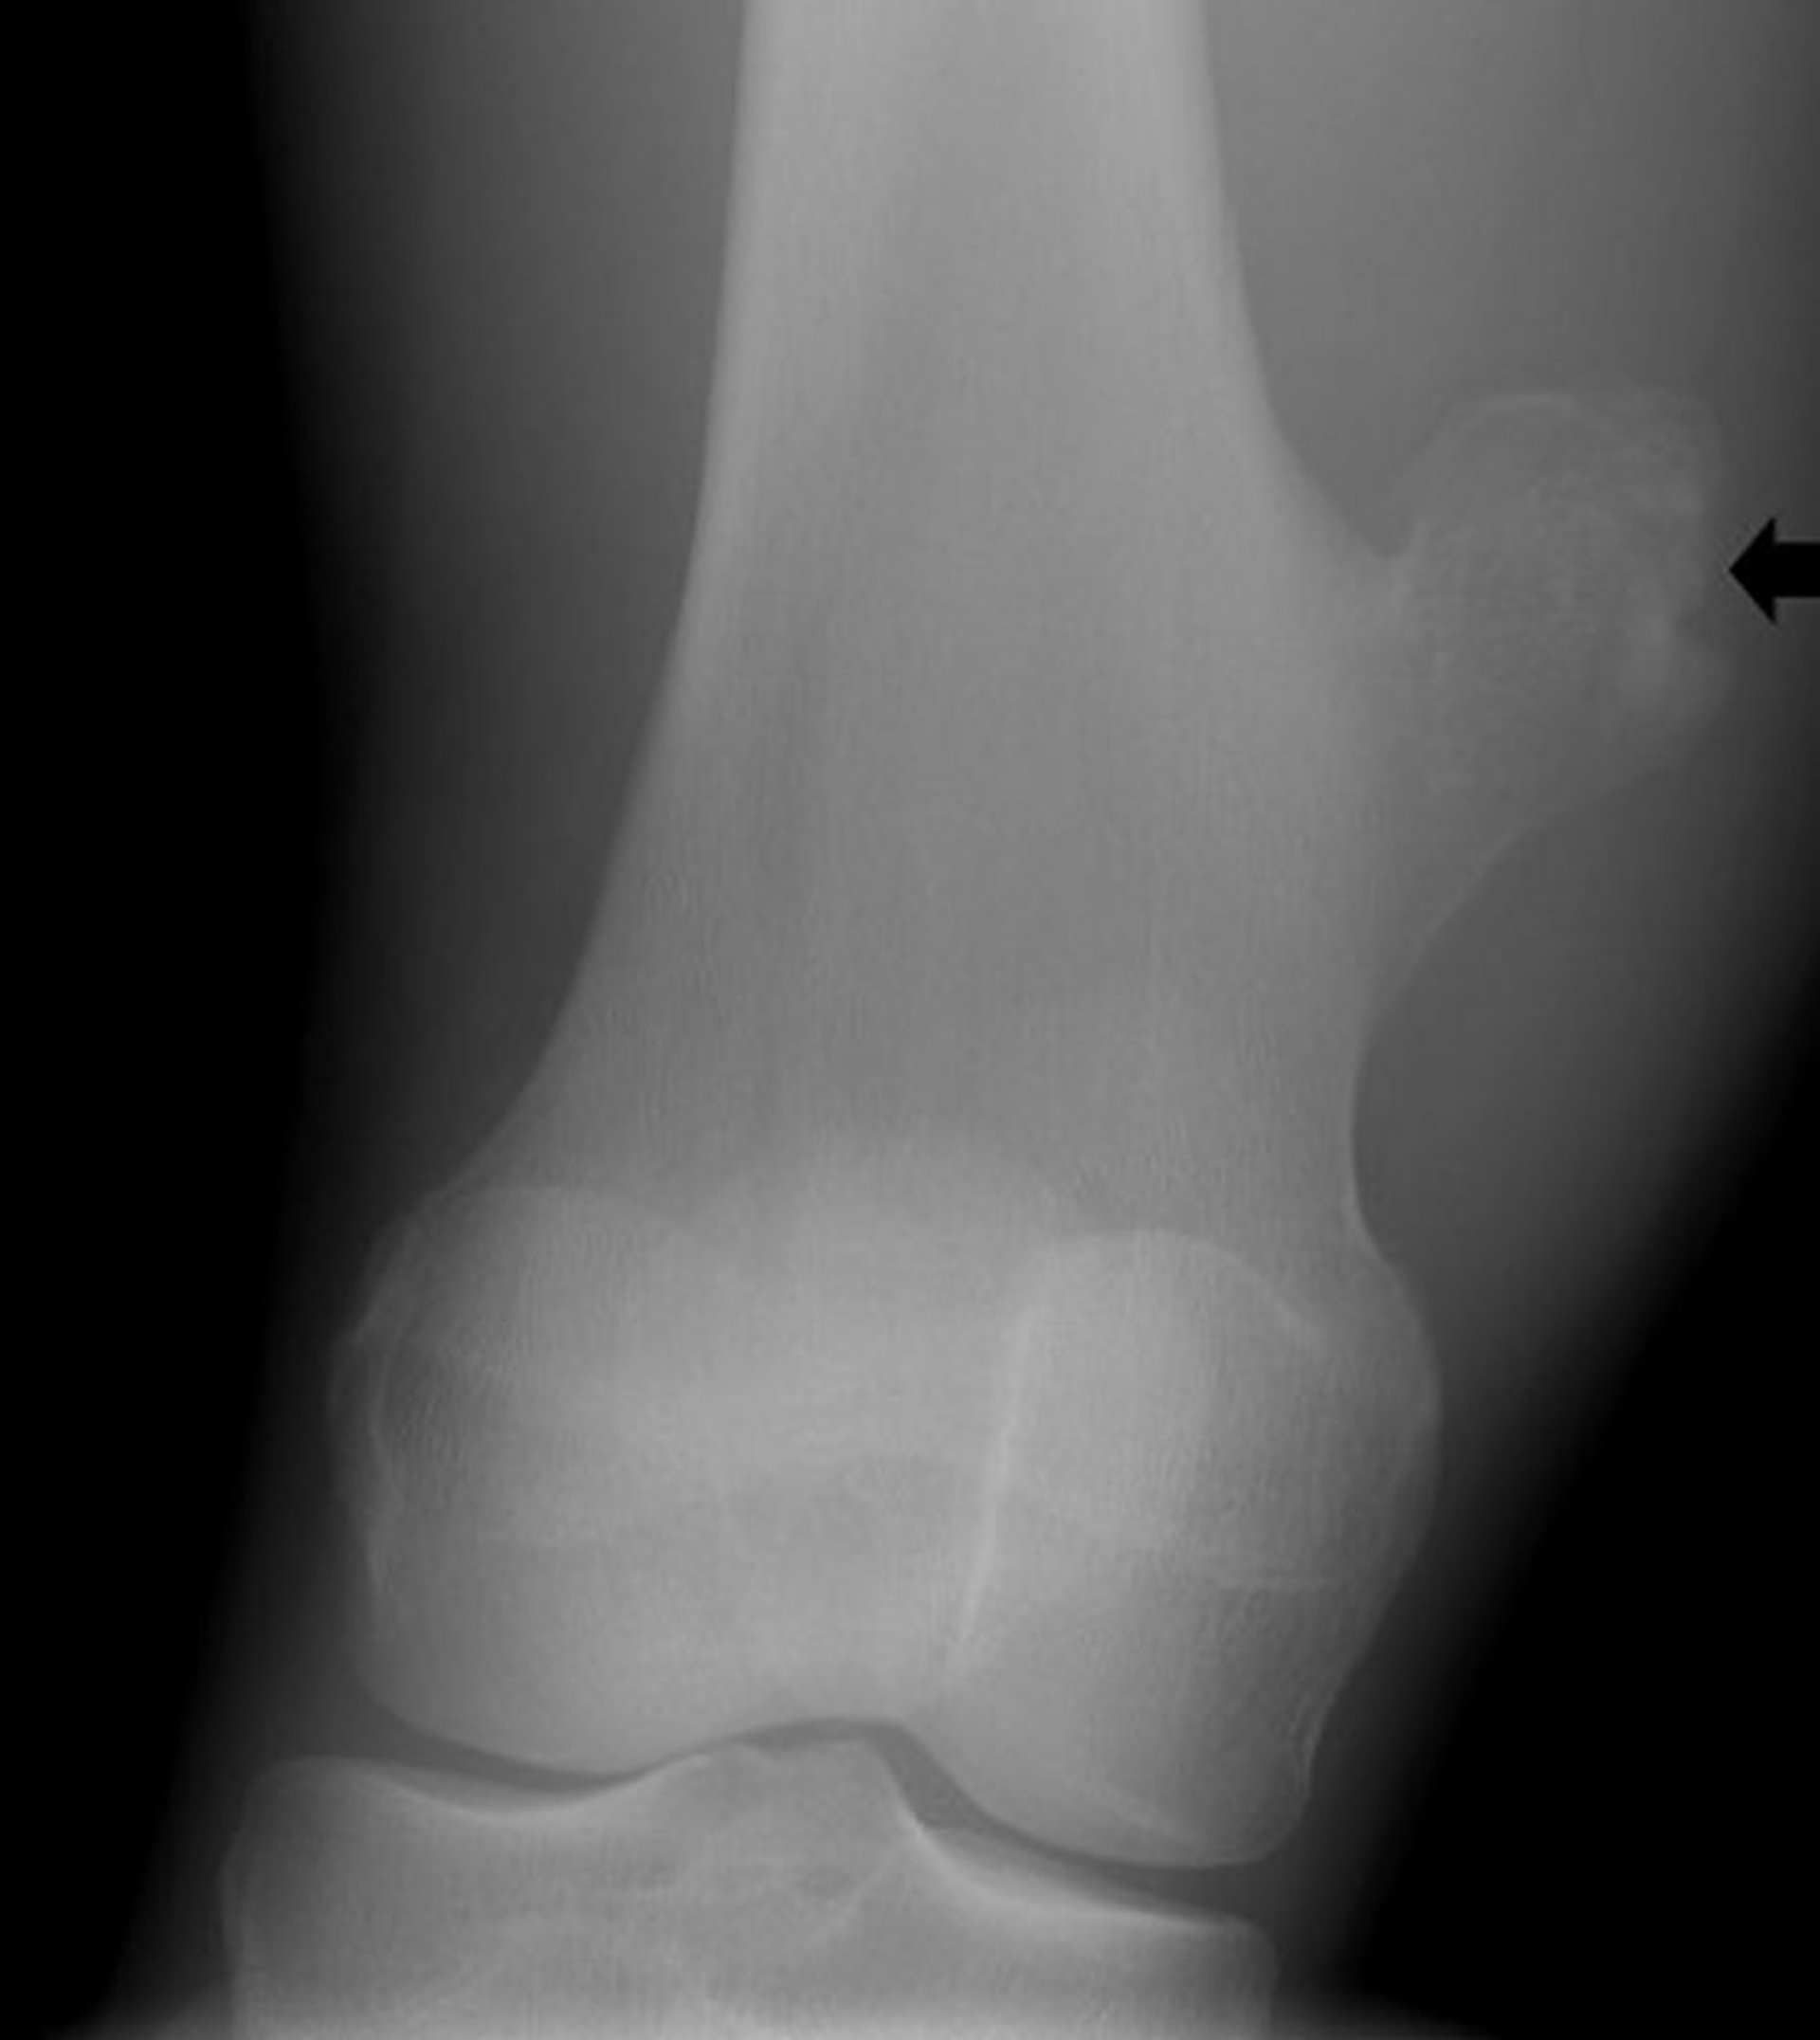

Остеохондрома колена

На данном рентгеновском снимке колена показан костный нарост (стрелка) из бедренной кости выше коленного сустава, что указывает на остеохондрому.

Image courtesy of Michael J. Joyce, MD, and Hakan Ilaslan, MD.